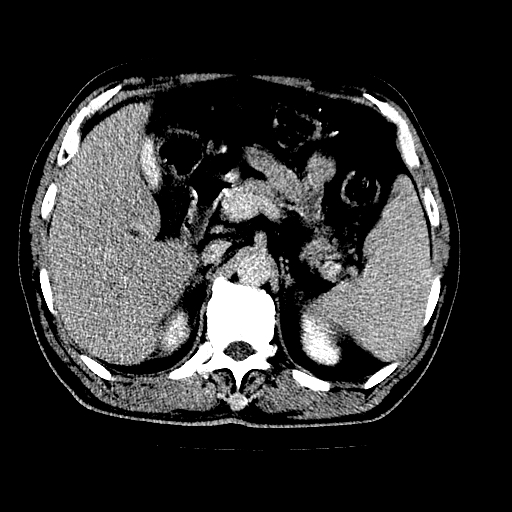

男,66岁,上腹部不适、黄染一周。彩超示:肝左叶占位,肝内胆管扩张,胆总管扩张,胆总管占位?

肝左叶不规则软组织肿块影,边缘不规整邻近肝实质受累分界不清;肝内胆管(左叶)明显扩张成“软藤状”,诊断:肝左叶胆管细胞癌。

左叶胆管细胞癌累及胆总管,门脉左支受侵,慢性胆囊炎胆结石,左肾小囊肿

胆囊缩小,其内胆汁浓缩,也提示梗阻部位应该位于胆囊管起始部以上或是胆囊管受累及,支持肝外胆管癌。